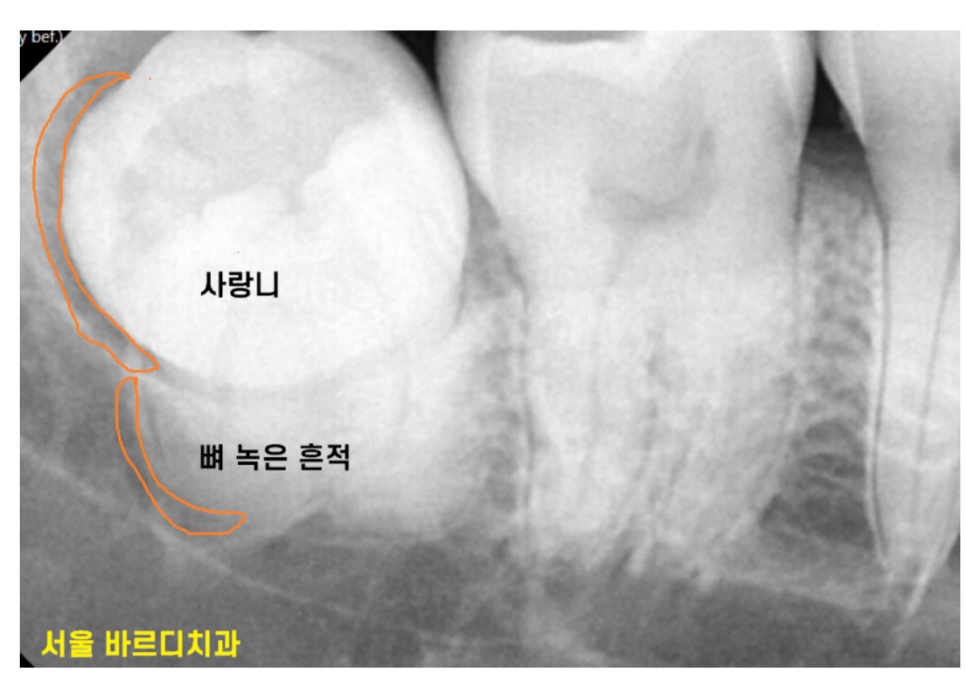

사랑니에 문제가 생기면서

주변 잇몸 뼈를 녹이는 경우를 쉽게 볼 수 있습니다.

230710

특히 부분적으로 사랑니가 맹출한 경우는

양치가 안되고 음식물이 끼다보니 더 그렇습니다.

사랑니로 인해 앞 치아가 썩거나

잇몸이 내려 앉는 경우가 많아요.